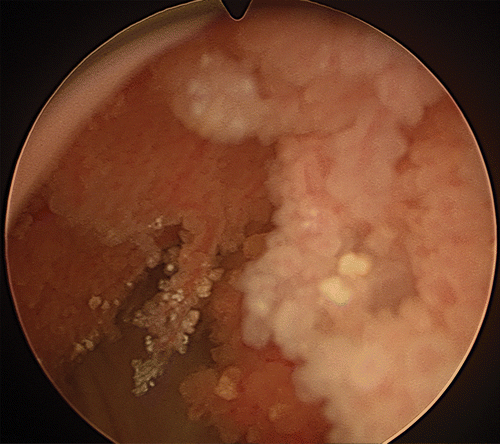

Picture of nephroblstomatosis + Wilms